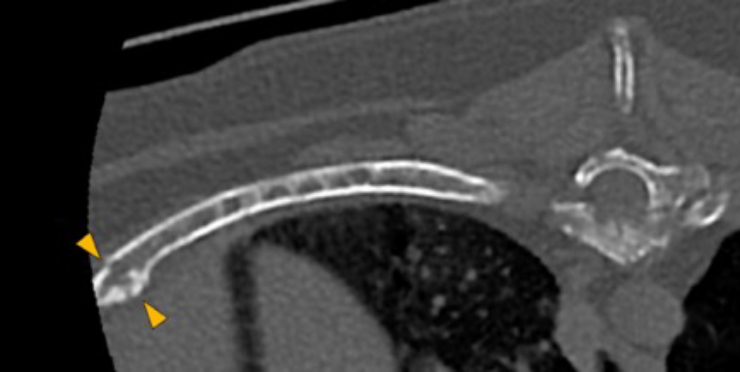

There are multiple osteolytic lesions with the same characteristics affecting both scapula and the pelvic bones included (pink and blue arrows respectively). There are osteolytic lesions with the same characteristics affecting multiple ribs. Associated with these lesions, there are multiple rib fractures.

Dog, thoracolumbar spine, ribs

10th and 12th rib